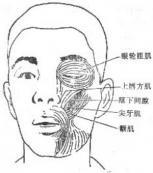

顳間隙感染

628健康網(wǎng)為您分享有關(guān)顳間隙感染的癥狀,顳間隙感染的治療方法,顳間隙感染的預(yù)防知識(shí),顳間隙感染的癥狀圖片,顳間隙感染...

眶下間隙感染

628健康網(wǎng)為您分享有關(guān)眶下間隙感染的癥狀,眶下間隙感染的治療方法,眶下間隙感染的預(yù)防知識(shí),眶下間隙感染的癥狀圖片,眶...

顳下間隙感染

628健康網(wǎng)為您分享有關(guān)顳下間隙感染的癥狀,顳下間隙感染的治療方法,顳下間隙感染的預(yù)防知識(shí),顳下間隙感染的癥狀圖片,顳...